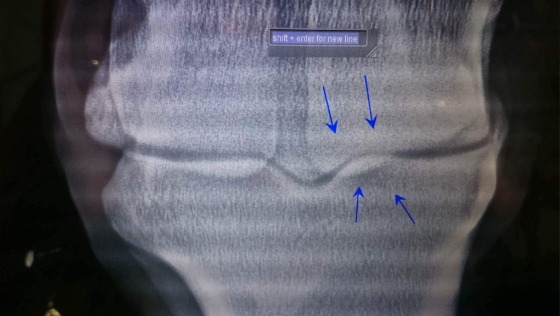

Kobyłka od pół roku stoi tylko na pastwisku ponieważ ma zdiagnozowaną przez lekarza weterynarii trwałą kontuzję przedniej kończyny która wyklucza ją z jakiego kolwiek użytkowania ponieważ każdy wysiłek nasila kulawiznę